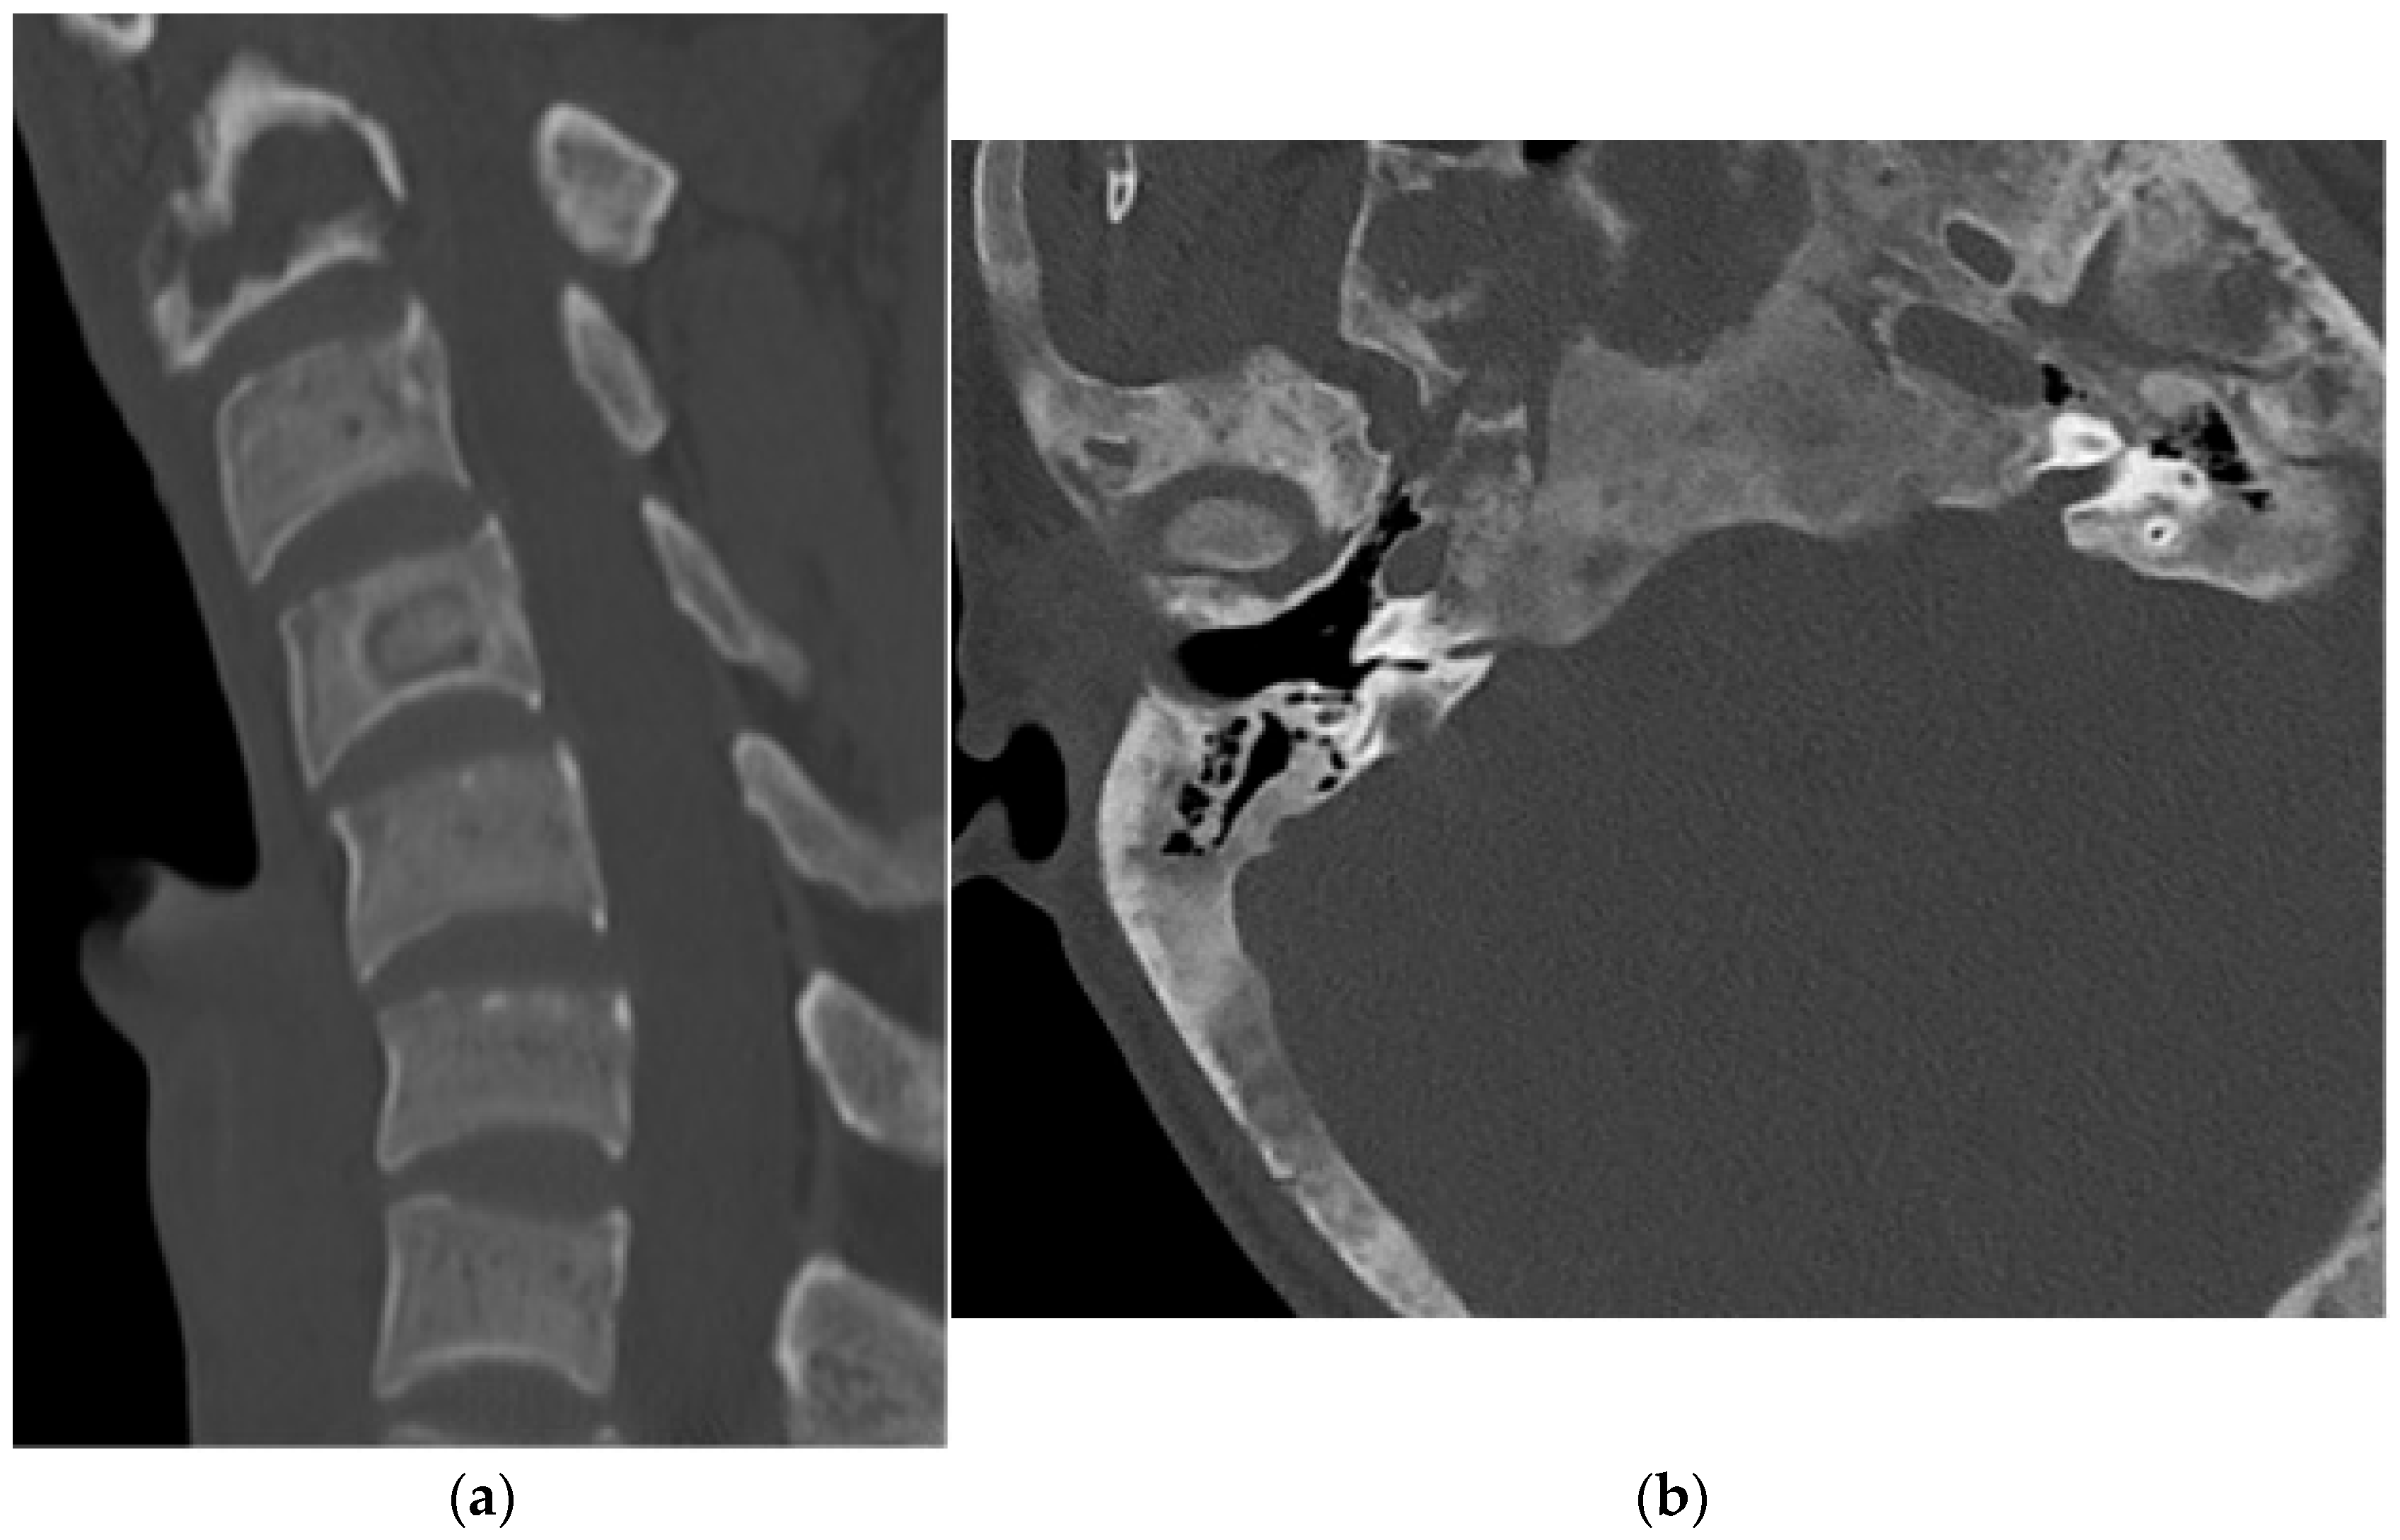

2.2.1. Osteochondroma